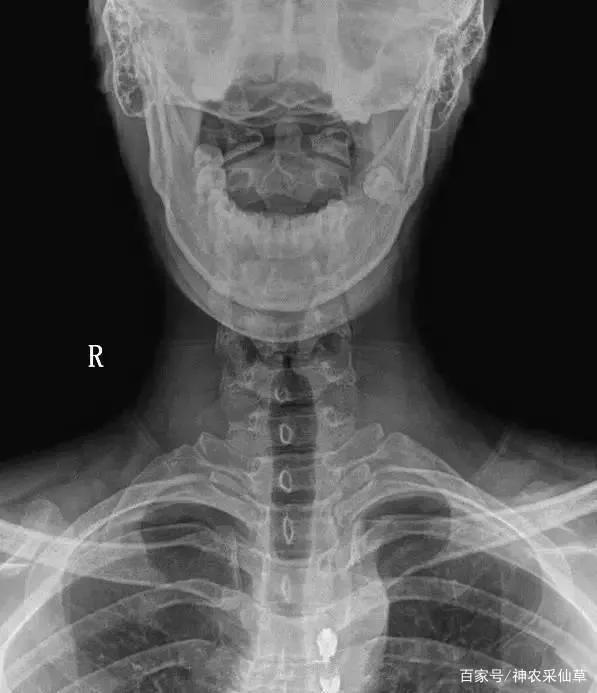

1、颈椎生理曲度变直或反弓。

颈椎生理曲度变直